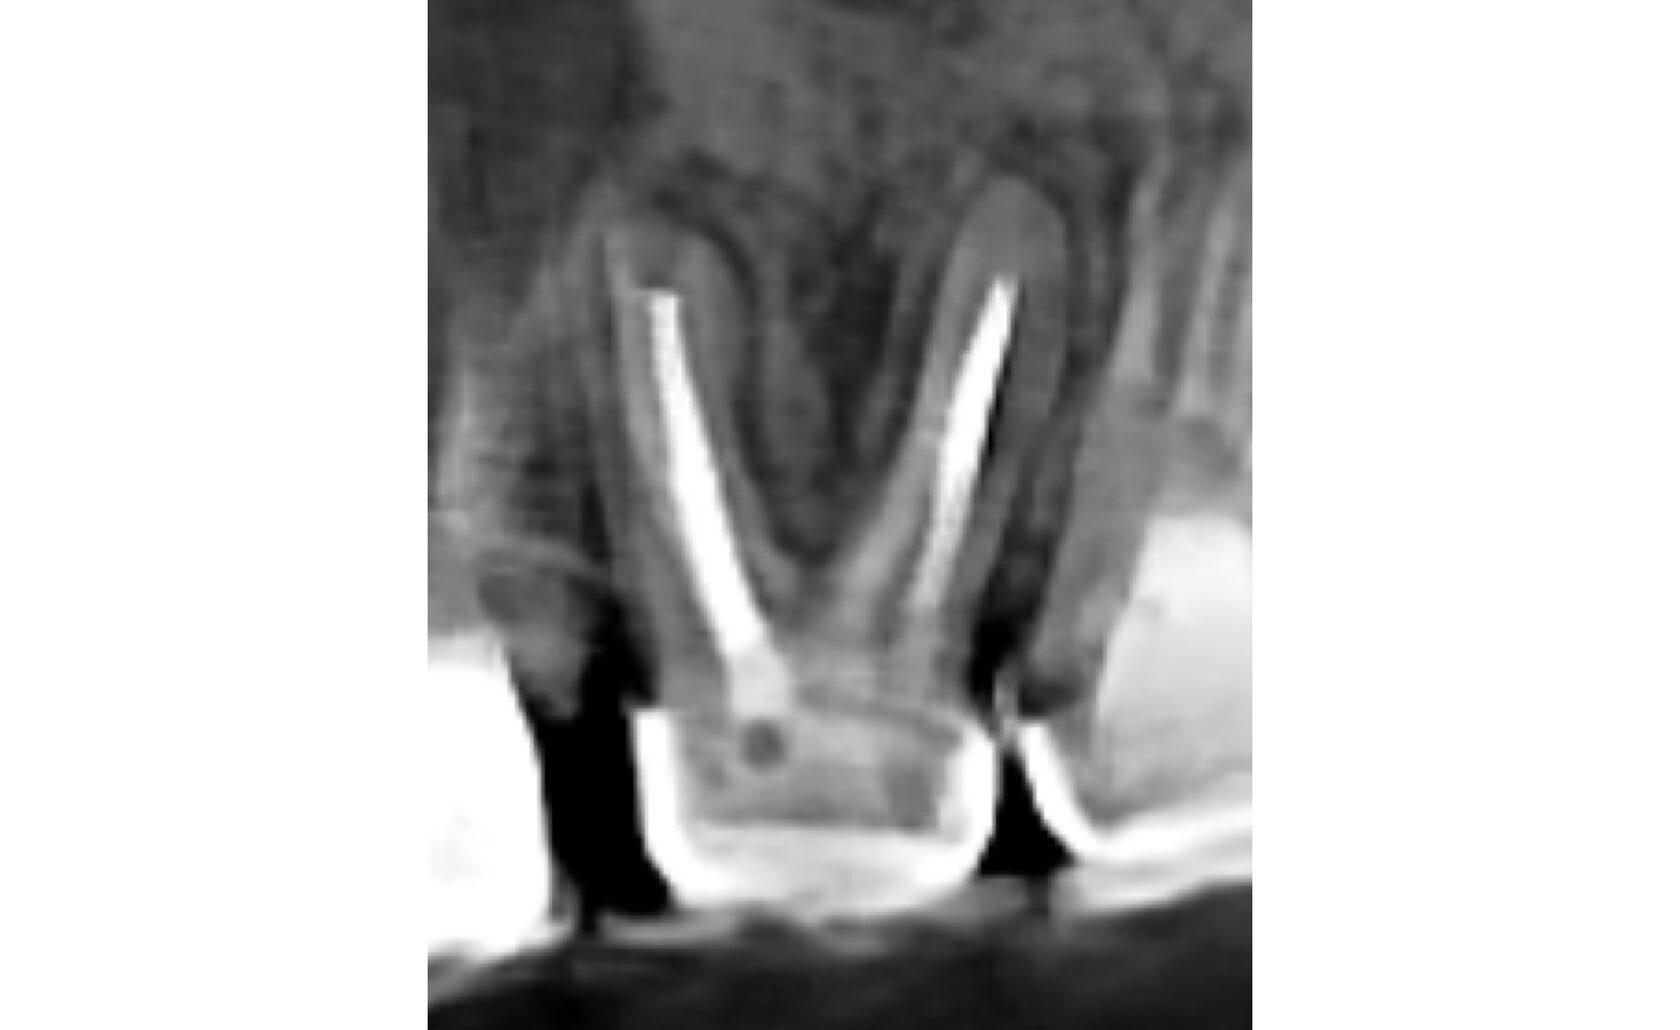

4. Во второе посещение выполнена обтурация и пост-эндодонтическая рестврация под ортопедическую конструкцию. (Фото 7,8)